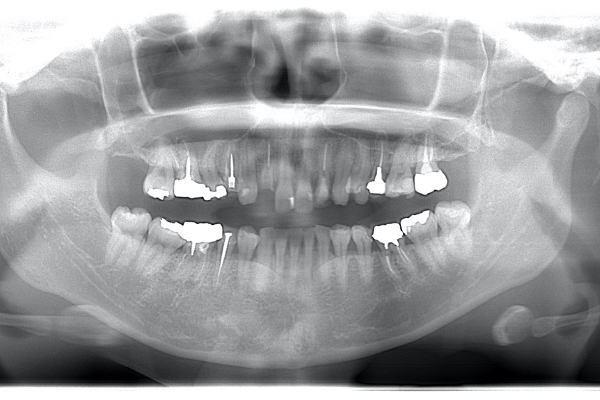

左上2は広範囲にわたってCRが充填されているのがわかります。またその周囲に透過像があり、カリエスになっていることもわかります。

| 根の中の薬が十分に充填されておらず、根の先が周りと比べて黒くなっており、炎症があると判断できます。 | 根の中にしっかりとお薬を緊密に充填しましたが、まだ根の先に黒くなっている部分があります。 |

レントゲンで見ても、右上2では歯質が歯肉縁上にのこっていない。しかし歯根は長いのでMTMの適応症例です。

| 治療前で歯根が長いのがわかります。歯根がある程度長く無いと、MTMは行えません。 | MTM終了時のもの。フックが上の金属に接している。また根尖に透過像があるが、歯が動いた証拠です。 |

残存歯質はないが、歯根は長いことを確認。